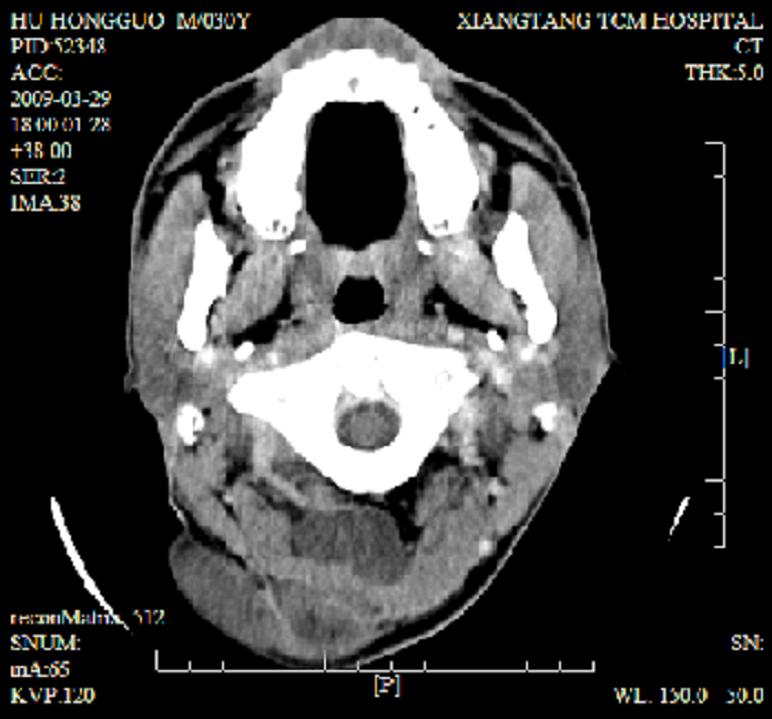

标题: CT19102:颈部肿块

男30y发现肿块3年

多处囊实性肿块,形态欠规则有一定形态,内见点状钙化,以囊变为主,增强后轻度强化,首先考虑神经源性肿瘤如鞘瘤,不除外脉管源性肿瘤如淋巴管瘤(见缝钻及囊性区域太多,如果合并感染完全可以这个影像表现),和海绵状血管瘤,但是血管瘤不太支持因为强化特征和病灶形态不典型.

右侧椎前间隙后部肌间、皮下囊性为主病变,可见分隔和点状钙化,分隔和壁呈轻度环形强化,大部分无强化。形态不规则,有钻缝特点。考虑1 淋巴管瘤合并感染2 血管平滑肌脂肪瘤3 表皮样囊肿4 不除外海绵状血管瘤。